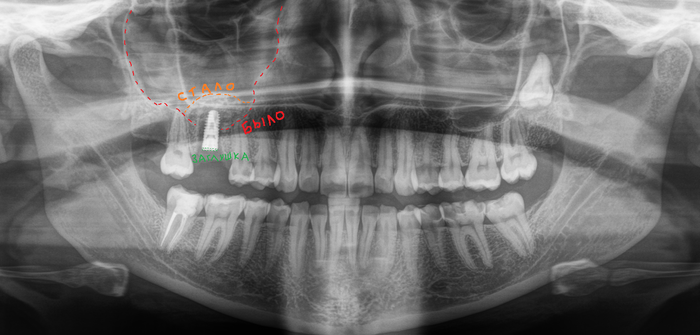

Ну и последний пример на сегодня — удаление 2-х зубов, установка 2-х имплантатов и синус-лифтинг.

Как мы видим условия в данном случае несколько хуже около 2мм. Но это не помешало нам провести операцию в полном объеме.